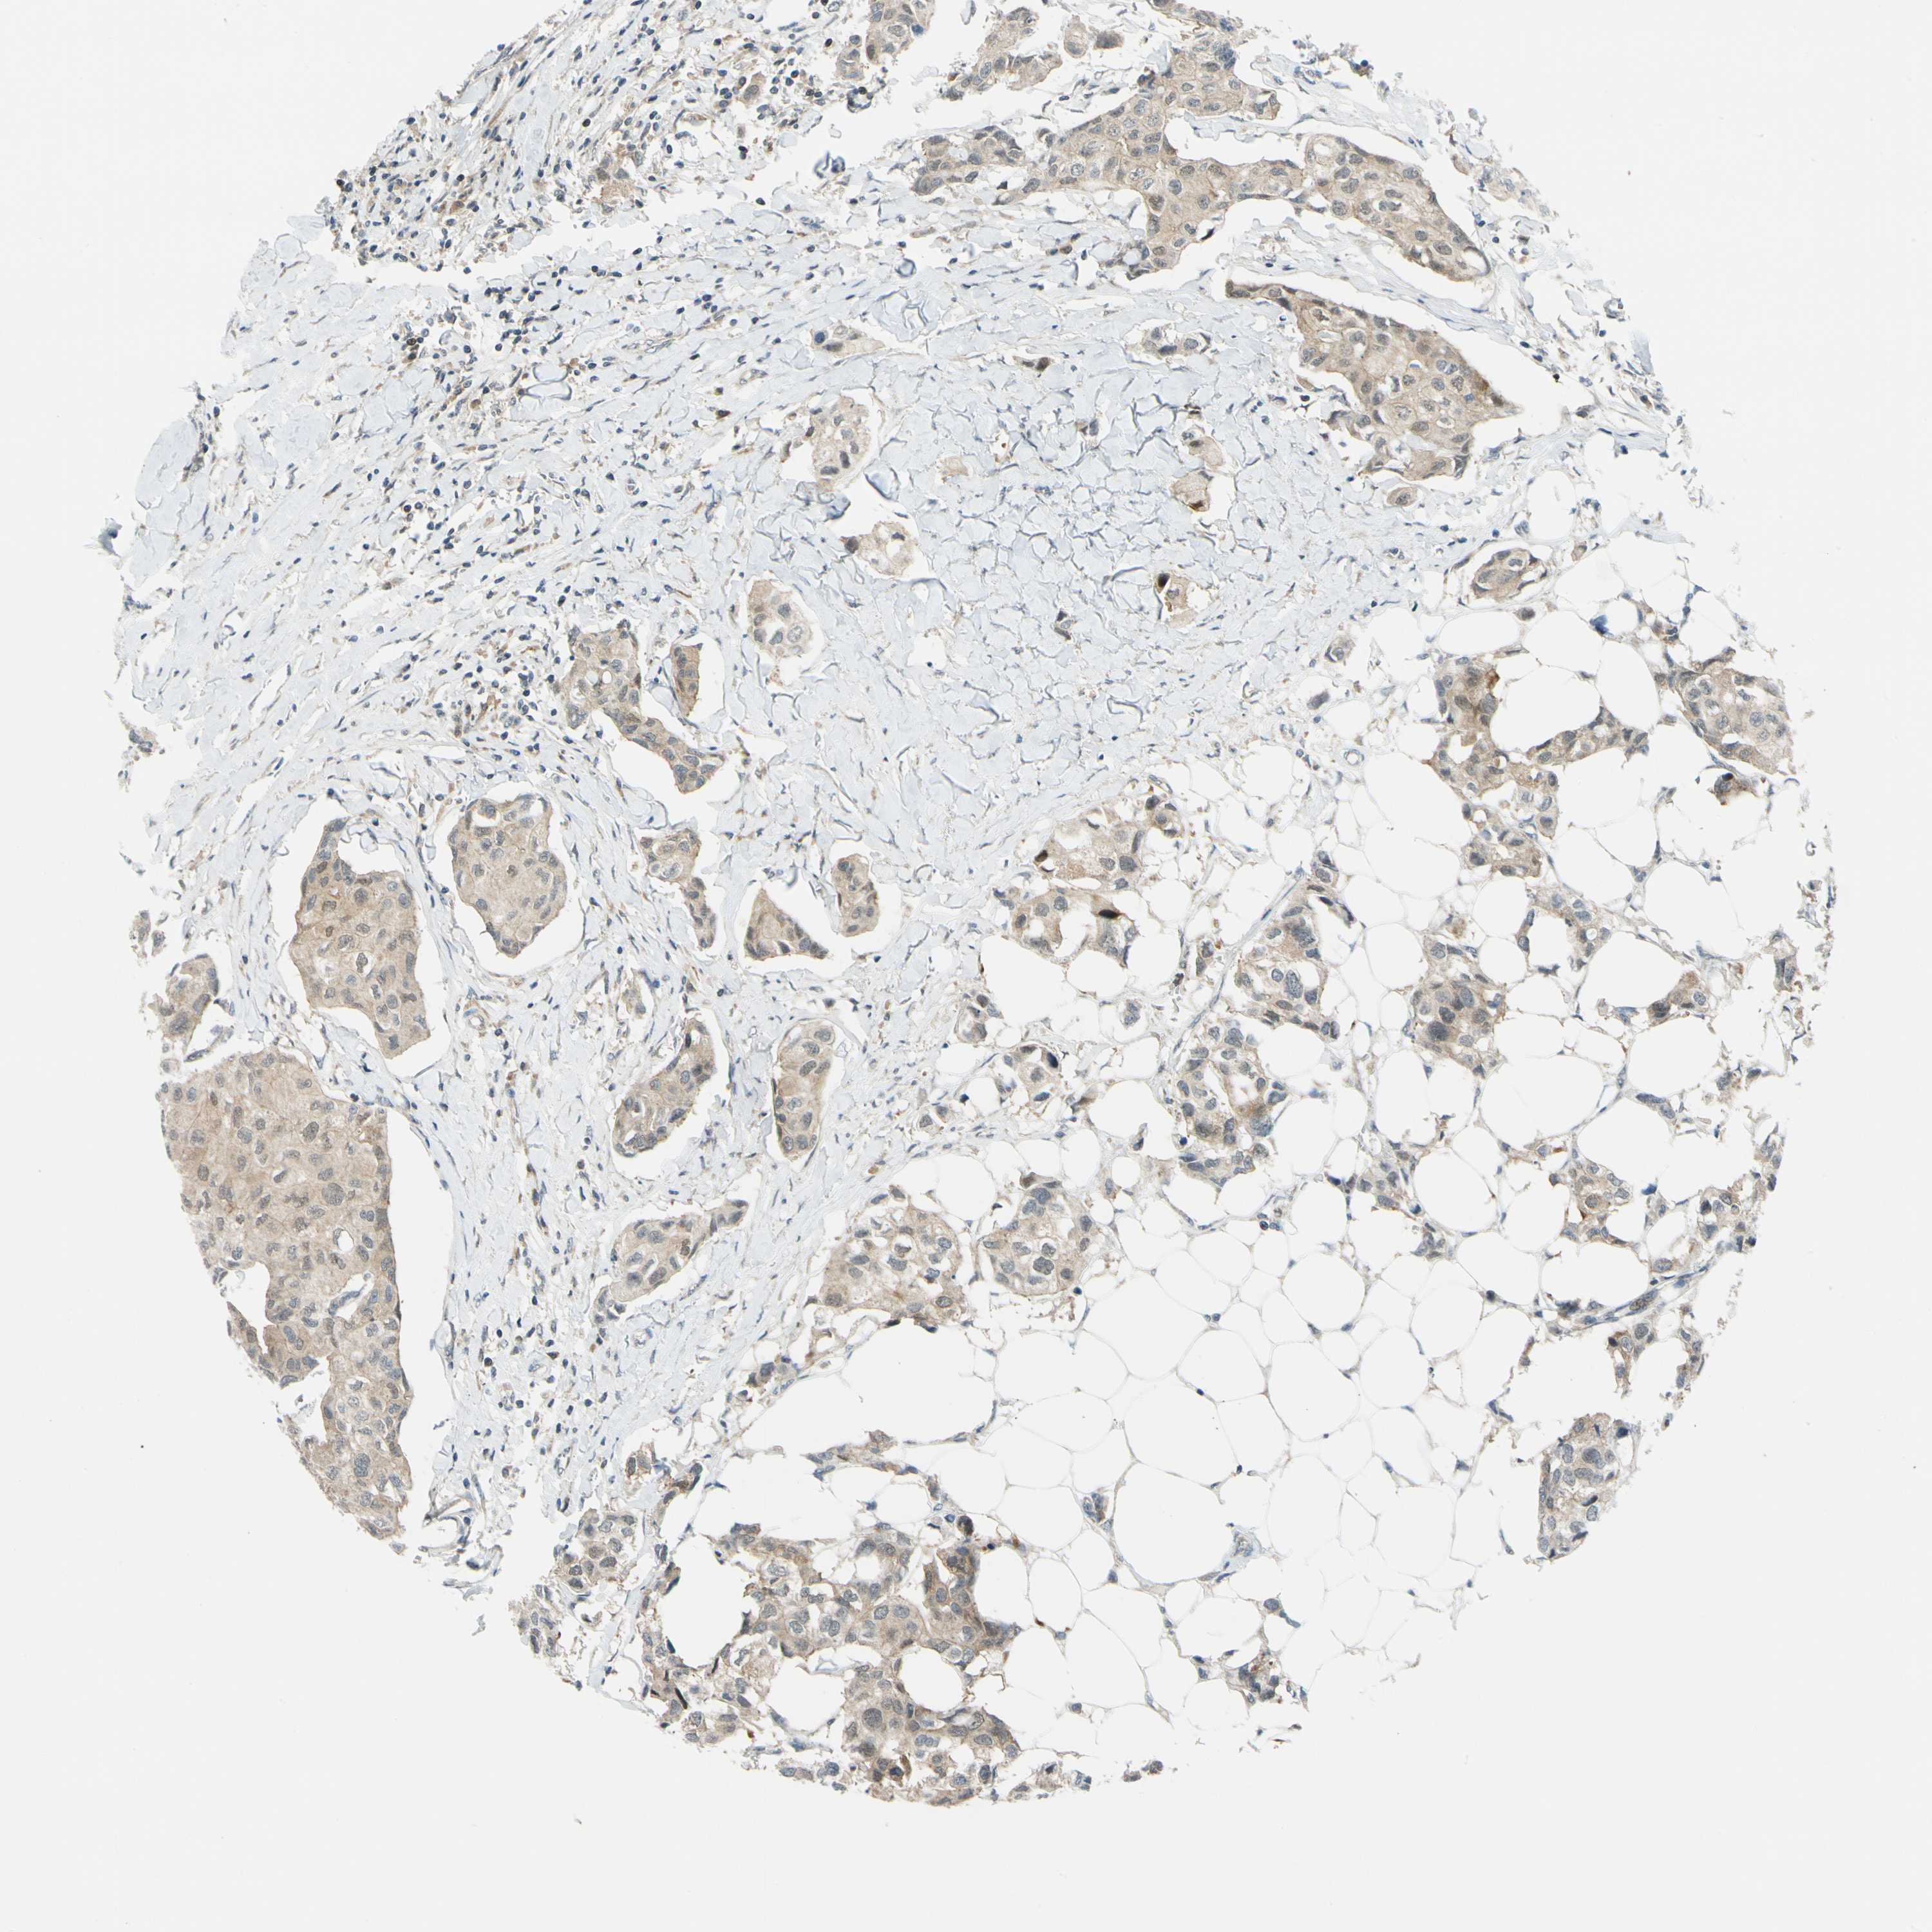

BRCA TCGA BRCA VALIDATION PROTEIN EXPRESSION